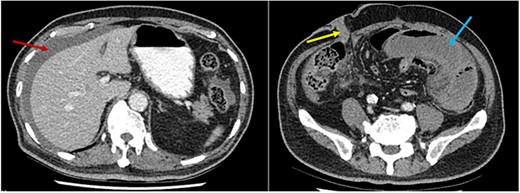

Histopathological examination confirmed ischaemic enteritis with patchy mural necrosis. Post-operative CT demonstrated healthy small bowel and patent left EIA (Figs 2 and 4). The patient recovered well and was discharged after a short hospital admission, with no ongoing abdominal symptoms or lower limb claudication. Follow up in the community was unremarkable with no further interventions required.

Post-operative CT scan. Series of sagittal images progressing from most medial (image A) to most lateral (image C). The patent EIA has been highlighted in yellow. Surgical clips are noted in image B (red arrow). Normal small bowel is noted in all images (blue stars).